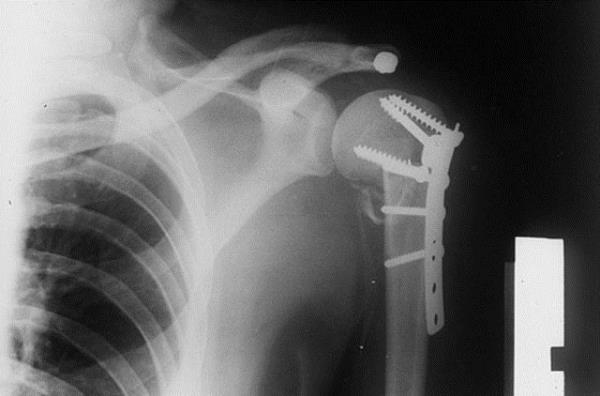

28. Omzu kırılan bir kişinin koluna yapılan müdahalenin görüntüsü...

Omzu kırılan bir kişinin koluna yapılan müdahalenin görüntüsü...